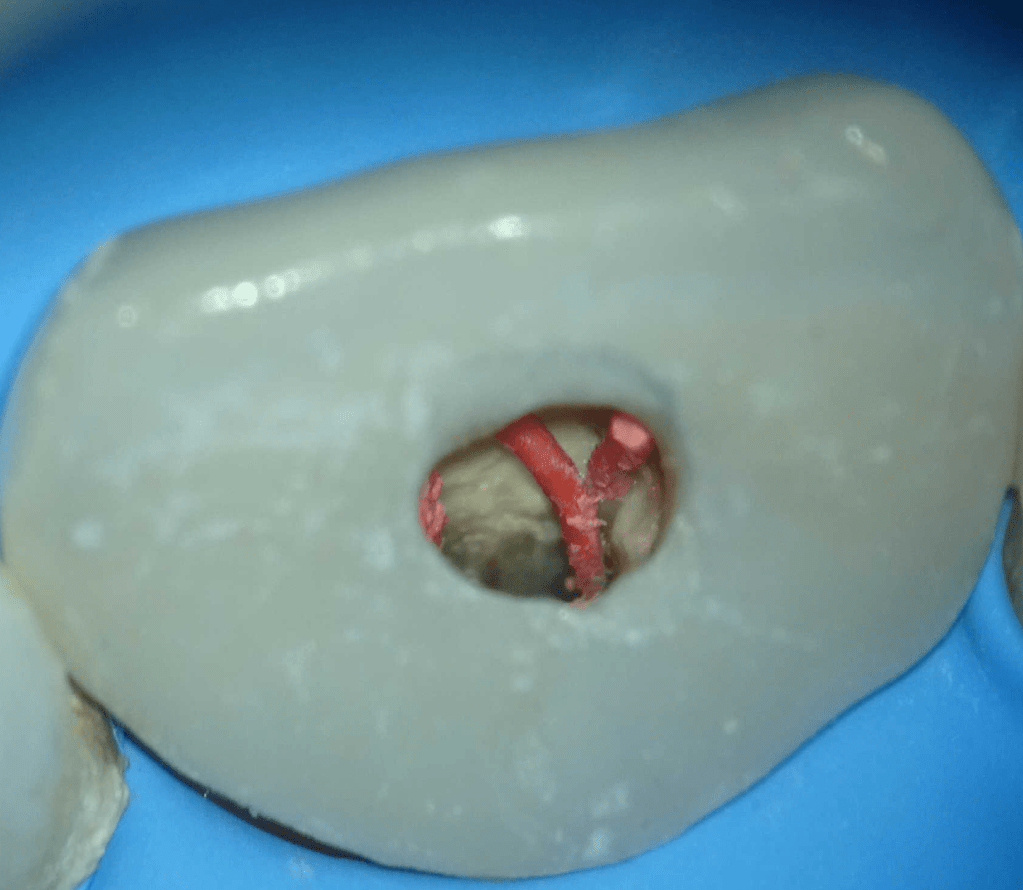

Pulpotomía biodentine + reco preendio